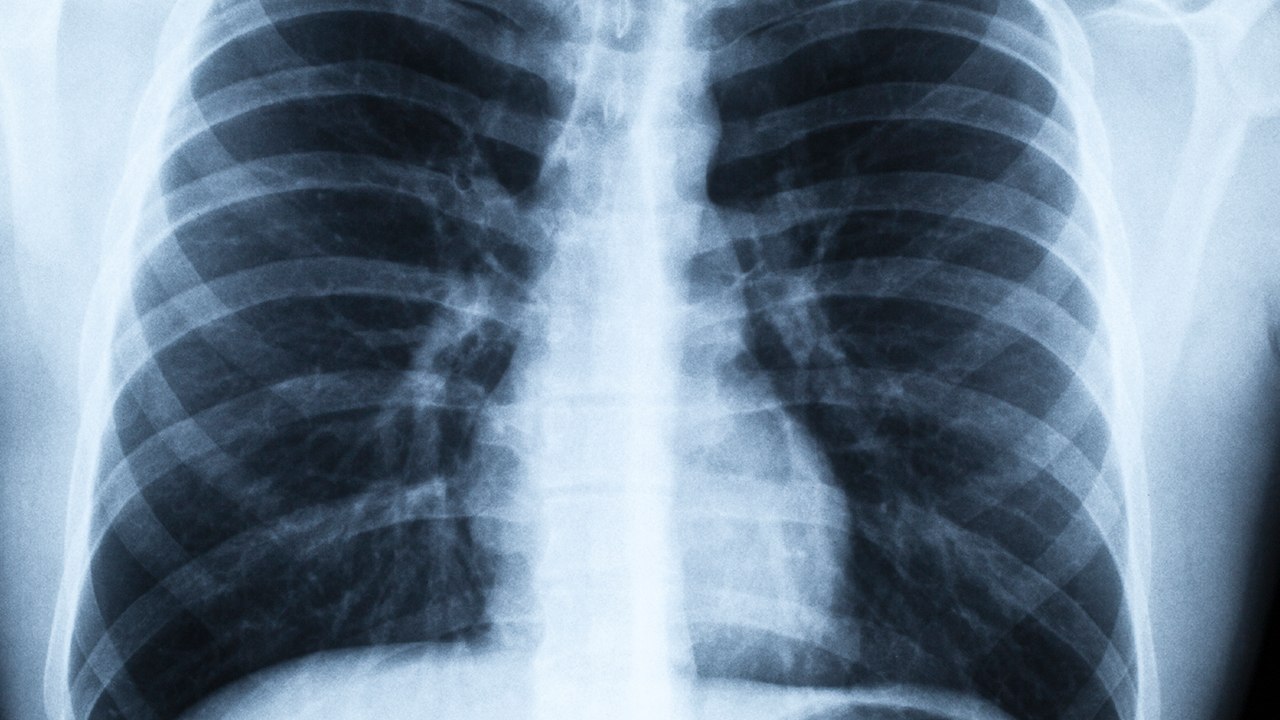

大葉性肺炎的診斷主要依靠臨床表現、胸部X線(xiàn)檢查和實(shí)驗室檢查。胸部X線(xiàn)檢查可見(jiàn)大片均勻致密陰影,與肺葉或肺段分布一致。實(shí)驗室檢查可見(jiàn)白細胞計數增高,中性粒細胞比例升高。痰涂片和痰培養可發(fā)現致病菌。治療上首選青霉素類(lèi)抗生素,如阿莫西林克拉維酸鉀片、氨芐西林膠囊等。對于青霉素過(guò)敏者,可選用大環(huán)內酯類(lèi)抗生素如阿奇霉素片、克拉霉素片等。重癥患者需住院治療,必要時(shí)給予氧療和液體支持。